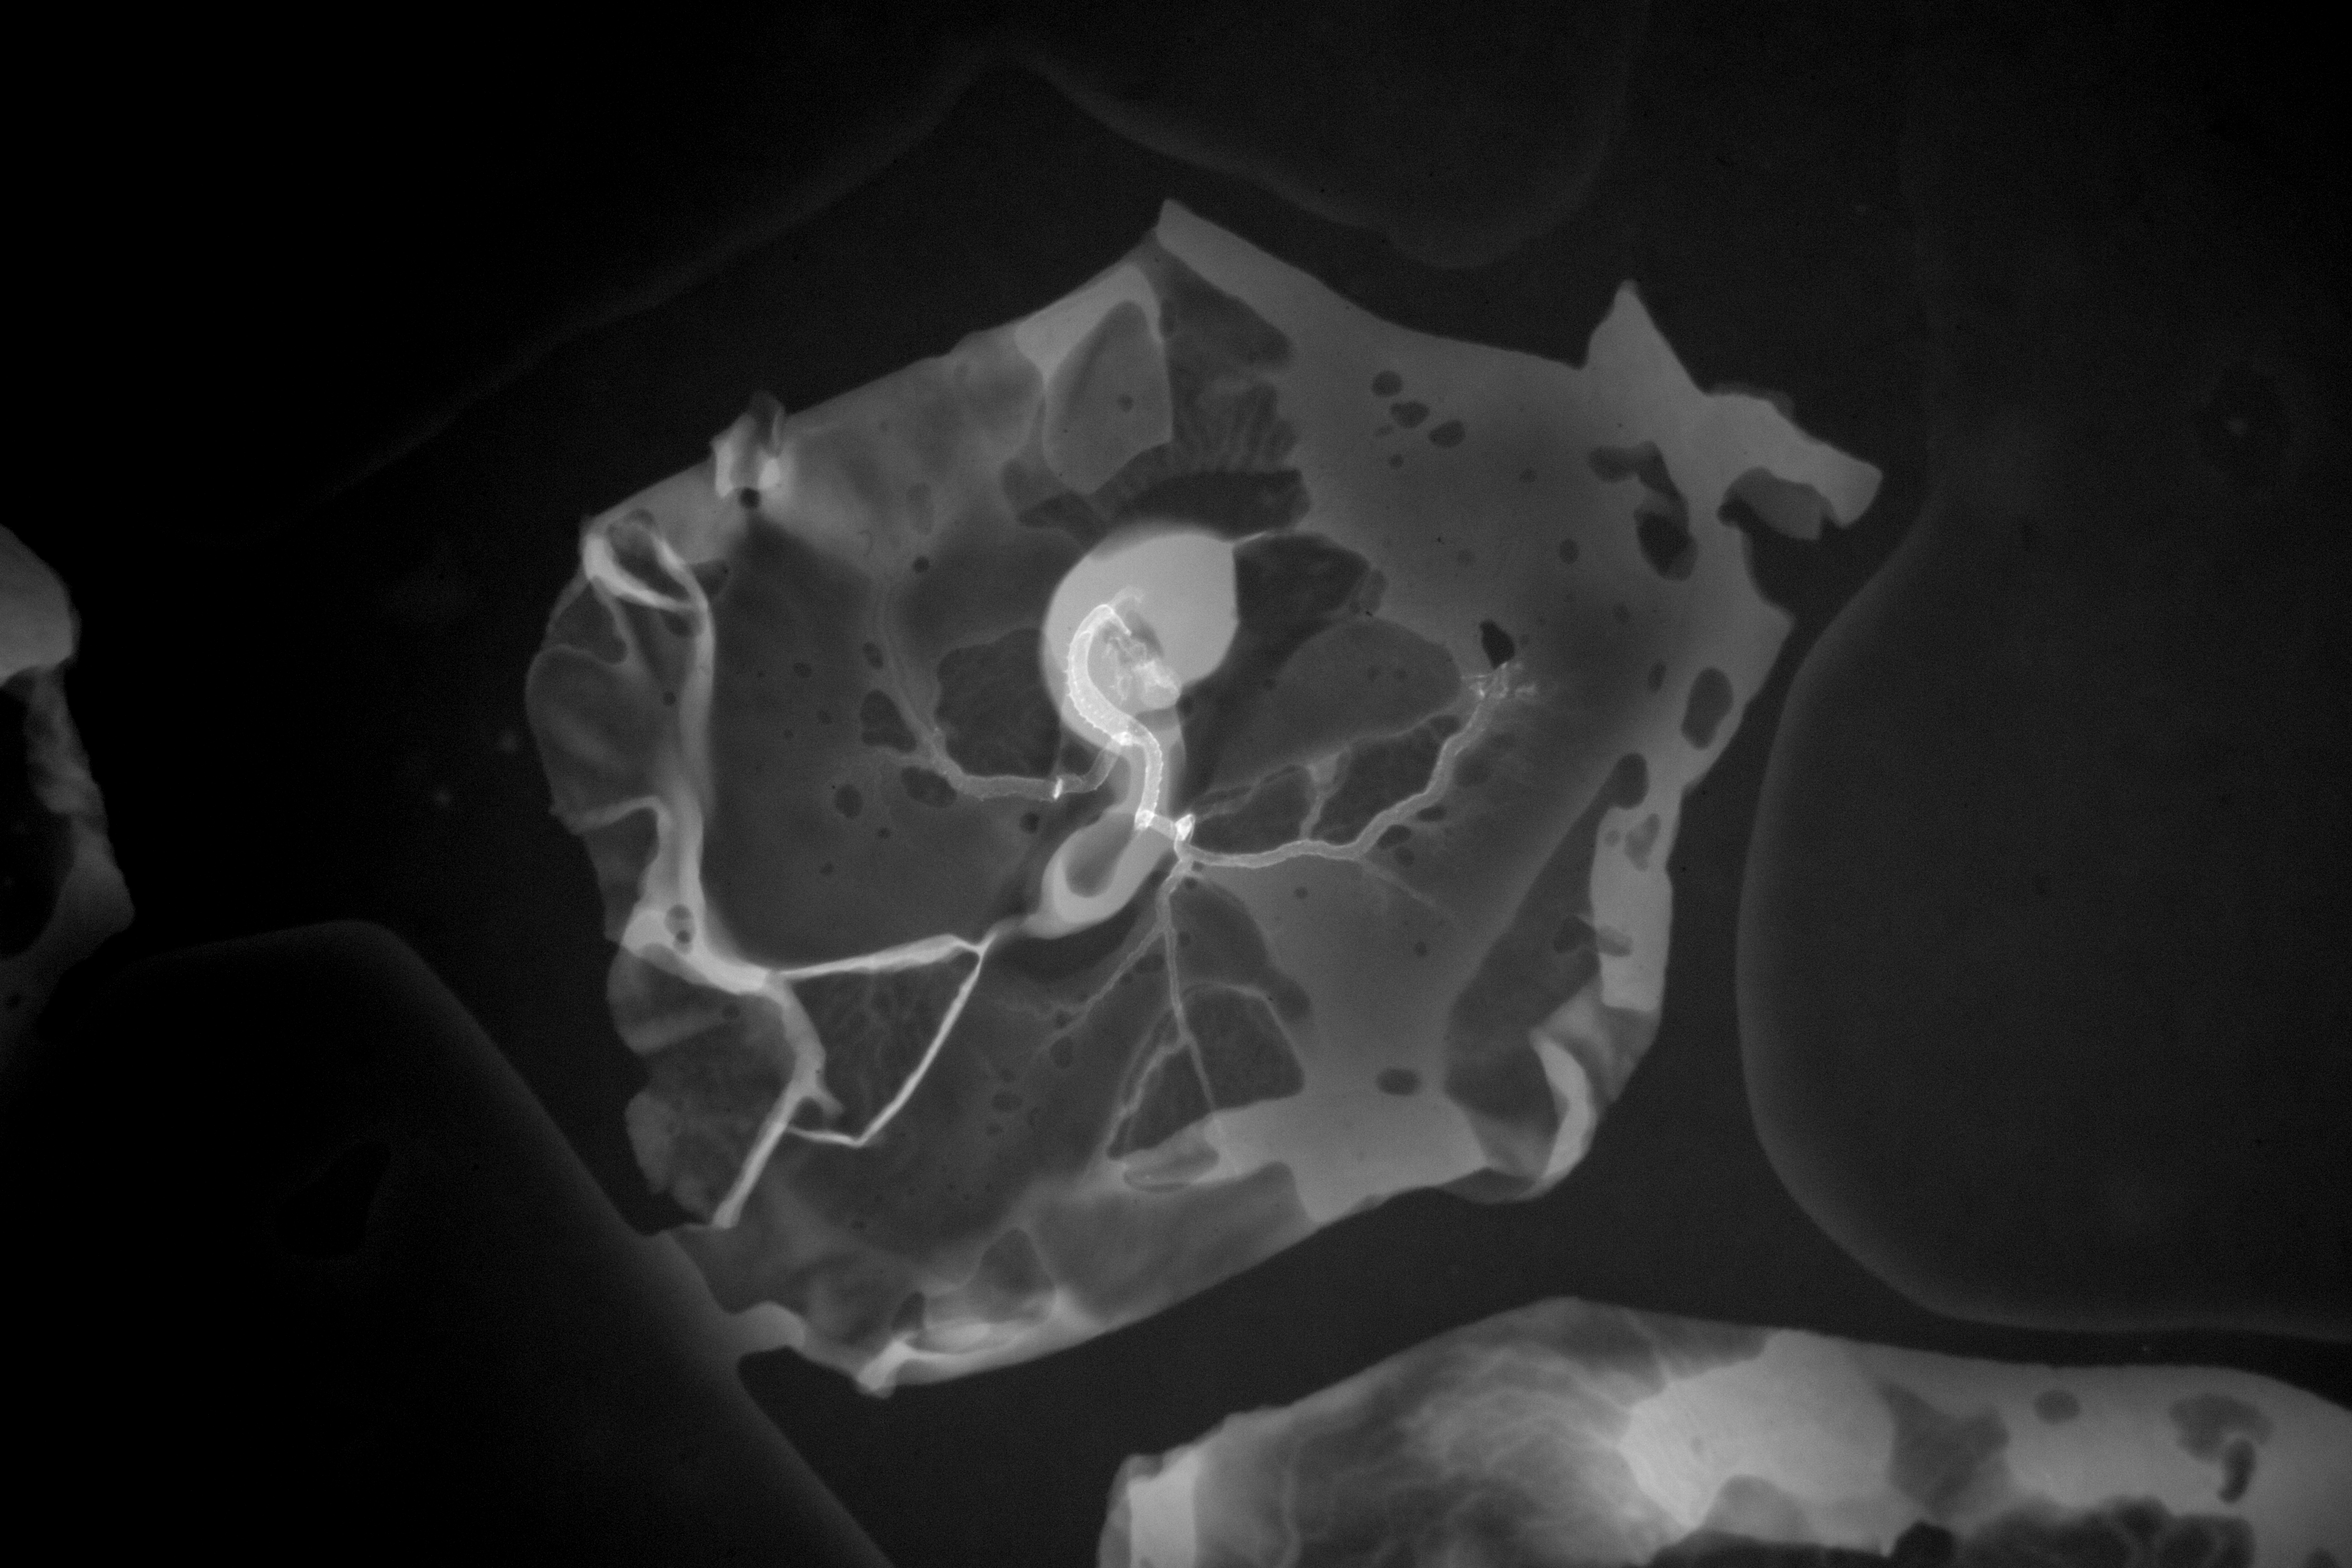

Chick Embryo Microangiography

Hamburger-Hamilton (HH) Stage 16 (approx. 2.1 - 2.5 days)

Stereo X-Ray Micrographs